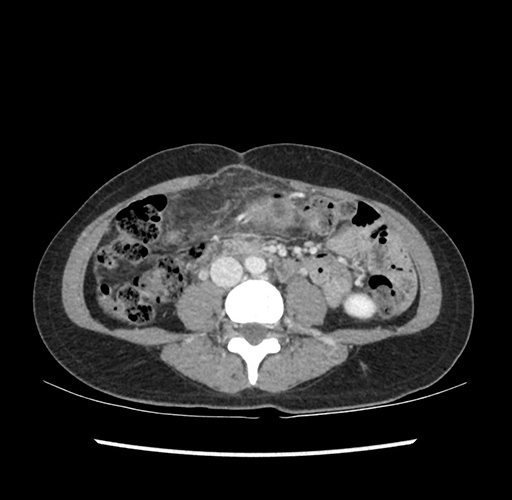

Imaging Analysis

Look through the patient's CT scan to identify any areas of concern for the necessary procedure.

Based on your CT findings, which issue(s) would give reason for "planned slowing down moment(s)" in this case?

Considering a standard left lateral sectionectomy procedure, what step(s) of the operation would you do differently in this case ?